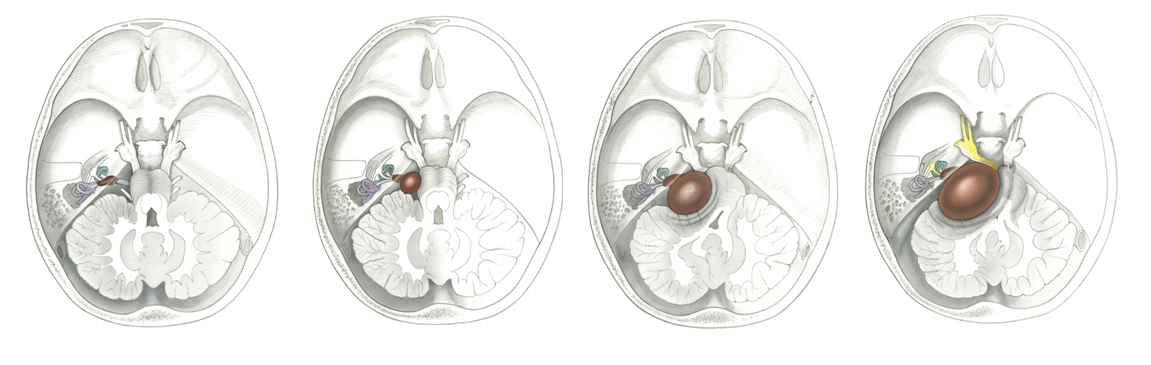

Différents stades du neurinome (d’après Jackler, ATLAS OF SKULL BASE SURGERY & NEUROTOLOGY. Thieme. ©2009)

Localisation d’un paragangliome du foramen jugulaire (d’après Jackler, ATLAS OF SKULL BASE SURGERY & NEUROTOLOGY. Thieme. ©2009 )